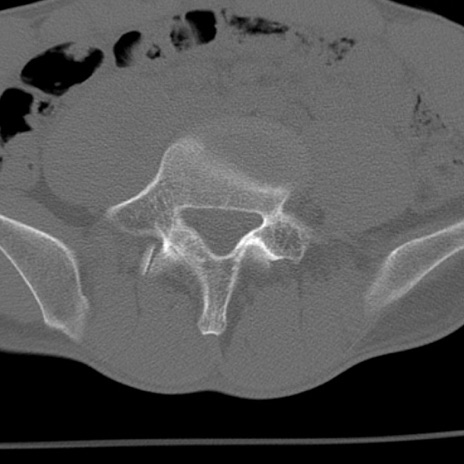

症例3 腰椎CT(横断像)

腰椎CT